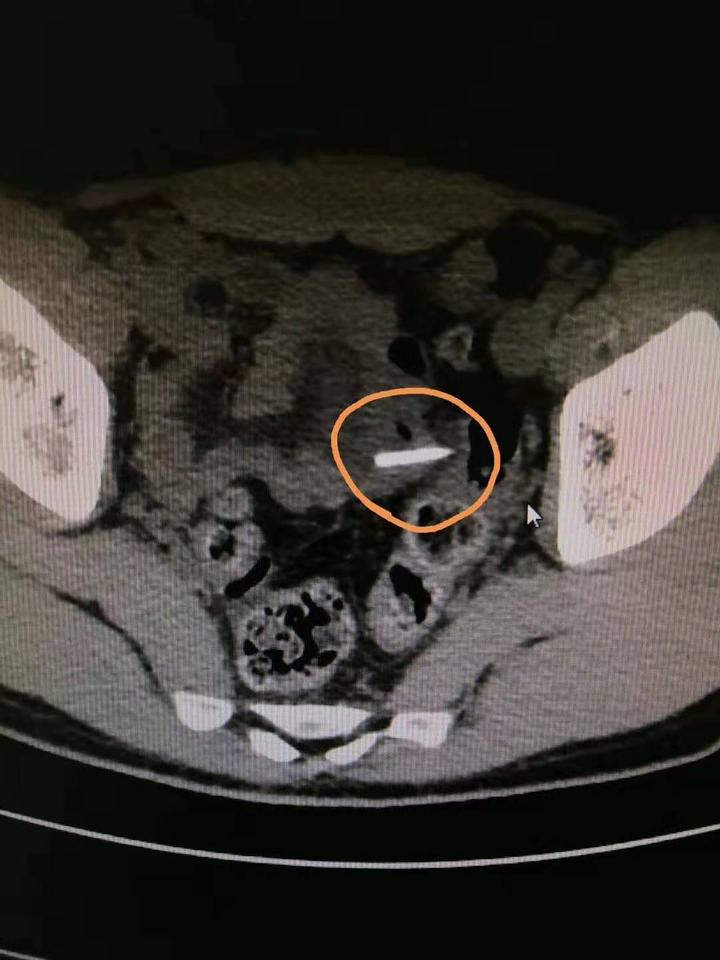

王师傅的影像资料

这就是王师傅误吞的甲鱼骨头。

医生立即为王师傅安排了手术。术中发现,王师傅的小肠上有一处穿孔,一根锋利的甲鱼骨头横卡在肠子内,已经把肠管刺穿,不少肠液流入腹腔,形成了腹膜炎。医生小心翼翼地将骨头取出,并为王师傅修补了破裂的肠壁,将脓液引流,冲洗腹腔。术后,王师傅康复状况良好。